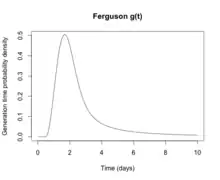

From a public health point of view, flu epidemics spread rapidly and are very difficult to control. Most influenza virus strains are not very infectious and each infected individual will only go on to infect one or two other individuals (the basic reproduction number for influenza is generally around 1.4). However, the generation time for influenza is extremely short: the time from a person becoming infected to when he infects the next person is only two days. The short generation time means that influenza epidemics generally peak at around 2 months and burn out after 3 months: the decision to intervene in an influenza epidemic, therefore, has to be taken early, and the decision is therefore often made on the back of incomplete data. Another problem is that individuals become infectious before they become symptomatic, which means that putting people in quarantine after they become ill is not an effective public health intervention.[197] For the average person, viral shedding tends to peak on day two, whereas symptoms peak on day three.[82]